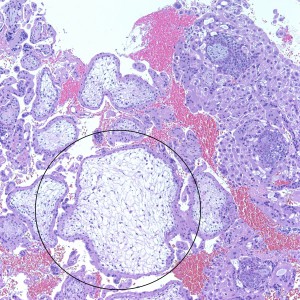

As we can see, enlarged and hydropic chorionic villi are not especially difficult to find (circle). None of these villi however demonstrate trophoblastic inclusions. There are rare interspersed small chorionic villi (top left) however they are generally rare.